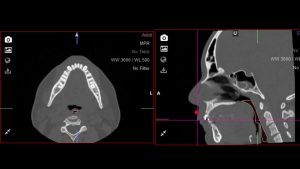

- tomografia;

- análise cefalométrica;

- avaliação da via aérea superior;

- espaço da via aérea superior;